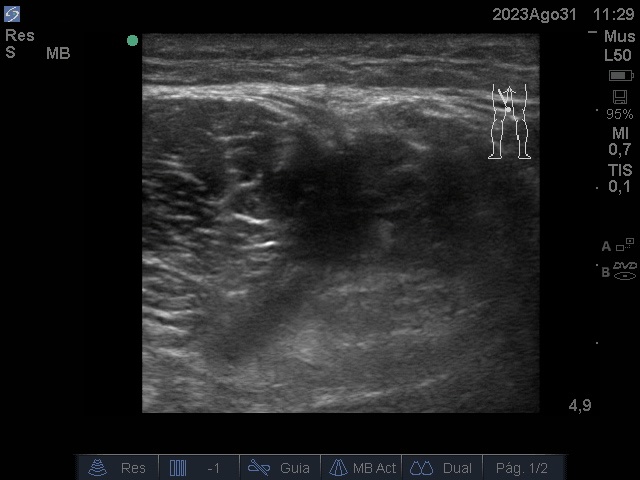

Ecografía: discontinuidad de la disposición de las fibras musculares normales a nivel del tercio medio de los cuerpos musculares isquiosurales que afecta al músculo semitendinoso del miembro ingerior izquierdo, edema focal e imágenes.

Anecogénicas intramusculares, sin captación doppler.

Se observa imagen anecoica irregular, elipsoide que se interpreta como sangrado entre el músculo semitendinoso y semimembranoso.